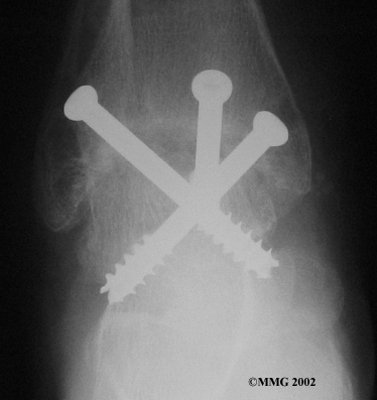

It is important when the surfaces are removed that the angles of the cut surfaces are correct. When the tibia is brought against the talus, the foot should be at a right angle to the lower leg. Once the cuts are made the bones must be held in place while they fuse. This can be done using large metal screws and metal plates if necessary. The screws are usually under the skin and are not removed unless they begin to rub and cause pain.

Inserting the screws

After ankle fusion, the physical therapists at FYZICAL Lakeville can help you learn to walk smoothly and without a limp. Although time needed for recovery varies among patients, an ankle brace will typically replace your cast after eight to 12 weeks. Your surgeon will take X-rays frequently to see if the bones are fusing together. You will probably need to use crutches during the time you wear the cast. As the fusion grows stronger, you will begin to put more weight on your foot when walking.